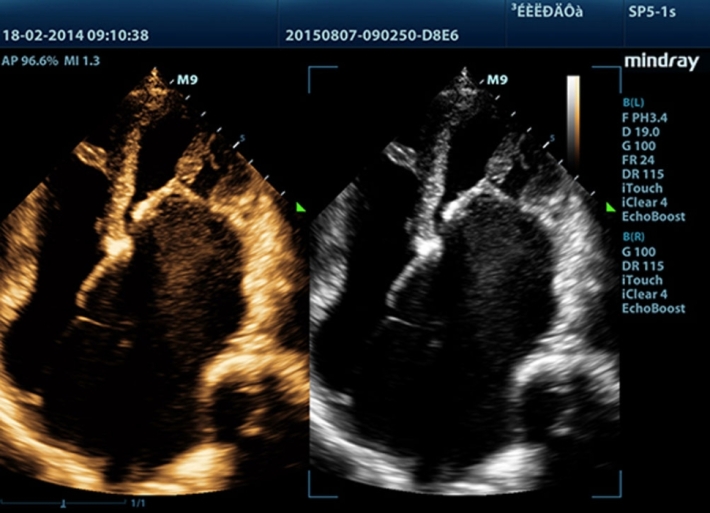

Медицинское оборудование и сервисное обслуживание